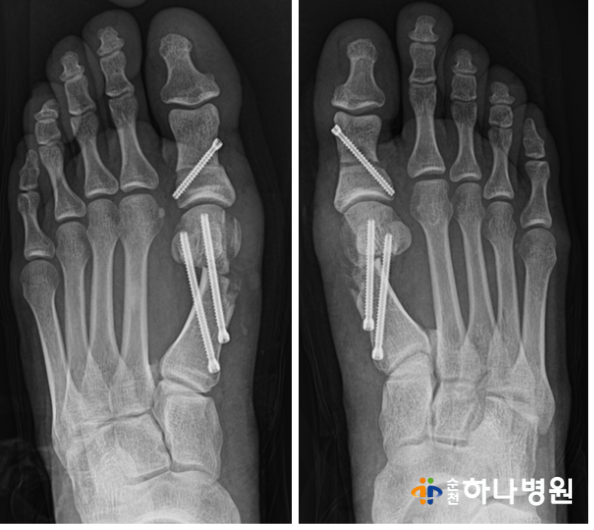

2) 수술직후 : 4세대 미타(MITA)로 교정

수술 직후 x-ray 사진입니다.

수술 전과 비교했을때 확연히

달라진 것을 확인할 수 있습니다!

4세대 무지외반증 수술 미타(MITA)는

2~3mm 정도의 미세한 구멍으로

특수 나사못을 이용하여 교정을 합니다.

실시간 영상장치를 보면서 특수기계를

삽입하여 세밀하게 뼈를 절골한 후

올바른 배열로 배치합니다.